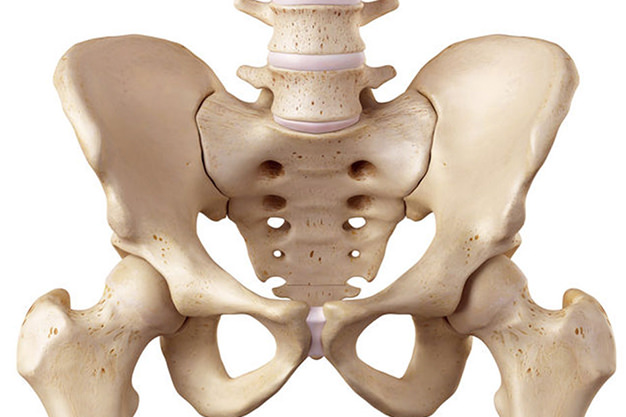

Graviditetsrelaterede bækkensmerter

Graviditetsrelaterede bækkensmerter

Graviditetsrelaterede bækkensmerter skyldes formentlig en øget belastning af bløddelene, dvs. muskler, sener og ledbånd, og muligvis hævelse af leddene. Der er altså ikke noget der indikerer, at man er blevet “løsere”. Undersøgelser viser at, hvis man tidligere har haft ondt i lænden, så har man en større risiko, for at få smerter i bækkenet under en graviditet. Endvidere er der fundet en øget risiko for smerter i bækkenet, hvis man er overvægtig, og hvis man er i dårlig fysisk form. Det er derfor vigtigt at blive ved med at træne, men på et niveau, som kroppen kan være med til.

Hvorfor får jeg bækkensmerter?

Graviditetsrelaterede bækkensmerter skyldes formegentlig en øget belastning af bløddelene, dvs. muskler, sener og ledbånd, og muligvis hævelse af leddene. Der er altså ikke noget der indikerer, at man er blevet “løsere”. Undersøgelser viser at, hvis man tidligere har haft ondt i lænden, så har man en større risiko, for at få smerter i bækkenet under en graviditet. Endvidere er der fundet en øget risiko for smerter i bækkenet, hvis man er overvægtig, og hvis man er i dårlig fysisk form. Det er derfor vigtigt at blive ved med at træne, men på et niveau, som kroppen kan være med til.